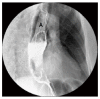

Rhabdomyomatous well-differentiated esophageal liposarcomas are extremely rare. As of August 2016, only one other such case has been reported in the English-language medical literature. Liposarcomas in general are one of the most common soft tissue neoplasms in adults, but the incidence of primary esophageal liposarcomas is exceptionally low. There have been only 42 reported cases of primary liposarcoma of the esophagus worldwide thus far. These malignancies are harbored within giant fibrovascular polyps, which slowly grow within the esophageal lumen causing obstructing symptoms. We hereby present the case of a 68-year-old male patient who came in with a 2-mo history of worsening intermittent dysphagia, persistent cough, and postprandial retrosternal pain. After an esophagogastroduodenoscopy, a computed tomographic scan, and a diagnostic endoscopy, complete endoscopic resection was performed of the 13 cm × 6 cm × 2.6 cm fibrovascular polyp. A literature review was done and results are presented herein.